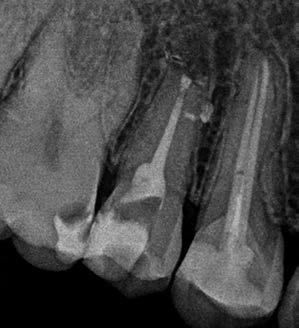

1. a-n. ábrák: Preoperatív CBCT-felvétel a bal alsó 6-os (3.6) fogról. Az axialis (a), coronalis (b) és sagittalis (c) nézeteken a mezialis és distalis gyökerek apicalis harmada körül sugáráteresztő zóna és ép buccalis corticalis csont látható. Egy olyan sablont terveztünk, amely jelezte a csontablak határait az apicalis terület pontos elérése érdekében (d). A mikrosebészeti bevatkozás során a sablont a helyére illesztettük (e), a csontablak határait megjelöltük (f) egy Piezotome CUBE LED kézi-darabba fogott fűrésszel, majd kivágtuk és eltávolítottuk (g és h) az apicalis területhez történő hozzáférés, illetve a mezialis és distalis gyökerek rezekciójának, retrográd preparációjának és retrográd gyökértömésének elvégzése érdekében (i). Végezetül a csontablakot visszaillesztettük és kollagén szivaccsal stabilizáltuk (j). A műtét után közvetlenül készített röntgenfelvétel a 3.6-os fogról (k). A kétéves kontroll során készített CBCT-felvétel: axialis (l), coronalis (m) és sagittalis (n) nézetek.

Egy 63 éves páciens korábban már kezelt bal alsó első nagyőrlőfogából (3.6) eredő mérsékelt fájdalom miatt kereste fel rendelőnket. A kórtörténetében panasza szempontjából releváns információ nem szerepelt. Az elkészült CBCT-felvételen a korábbi kezelések során észre nem vett, jelenleg feltáratlan meziobuccalis csatornát, valamint a mezialis és distalis gyökerek körül kialakult periapicalis elváltozást, és ezt a léziót borító intakt buccalis corticalis csontlemezt láttunk.

A fog revideálását és újbóli gyökértömését két ülésben végeztük el. A régi gyökértömés eltávolítását, valamint mindhárom gyökércsatorna megmunkálását és fertőtlenítését követően kalcium-hidroxid alapú gyógyszeres zárást helyeztünk a gyökércsatornákba. A gyökértömés egy héttel később került behelyezésre. A páciens panaszai két hónap elteltével sem szűntek.

Klinikai vizsgálat során vertikális kopogtatási érzékenységet jelzett. A fog körül mérhető szondázási mélység és a fogmobilitás fiziológiás volt. A CBCT-felvételen nem észleltünk a csontos regeneráció megindulására utaló jeleket (1. a–c. ábrák). A korábban gyökérkezelt, gyökértömött és revideált 3.6-os fog esetében az alábbi diagnózis került felállításra: periodontitis periapicalis symptomatica. A panaszokat okozó fog további ellátása során navigált endodonciai mikrosebészetet kívántunk alkalmazni. Az alsó állcsontról intraorális szkent (TRIOS, 3Shape) készítettünk, és a felszíni topográfiát tartalmazó STL fájlt, valamint a CBCT-felvétel készítése során nyert DICOM fájlokat a Blue Sky Bio szoftver segítségével egyesítettük. A sebészi sablon megtervezésére az így kapott háromdimenziós képet használtuk. A sablon kialakítása során arra törekedtünk, hogy a sablon egyértelműen meghatározza a gyökércsúcsi terület eléréséhez szükséges csontablak határait (1. d. ábra)

A beavatkozás során helyi érzéstelenítésben teljes vastagságú mucoperiostealis lebenyt képeztünk, és a sablon segítségével bejelöltük a preparálandó csontablak határait. Az ablak széleinek megfelelően Piezotome CUBE LED kézi-darabbal (ACTEON) a kortikális teljes vastagságában vágást ejtettünk, majd az így kapott csontlemezt (ablakot) eltávolítottuk (1. e–h. ábra), és ezt követően steril fiziológiás sóoldatba helyeztük. A rezekció elvégzését követően (1. i. ábra) a mezialis csatornákat ultrahangos eszközök segítségével (NSK) retrográd irányból preparáltuk, majd az így kialakított mélyedésbe retrográd gyökértömést készítettünk. A tömés anyagául az EndoSequence BC RRM Fast Set Putty-t (Brasseler) választottuk. A tömés elkészítését követően a csontablakot visszaillesztettük, és a stabilizálása érdekében a vágásoknak megfelelően kialakult résekbe kollagén szivacsokat (Collagen Tape, Zimmer Biomet) helyeztünk (1. j-k. ábra). A lebenyt 6/0-s Prolene varratokkal (Corpaul) rögzítettük.

A kétéves kontroll során elvégzett klinikai és radiológiai vizsgálat (CBCT-felvétel) a periapicalis elváltozások megszűnését és a corticalis csontállomány tünet- és szövődménymentes gyógyulását